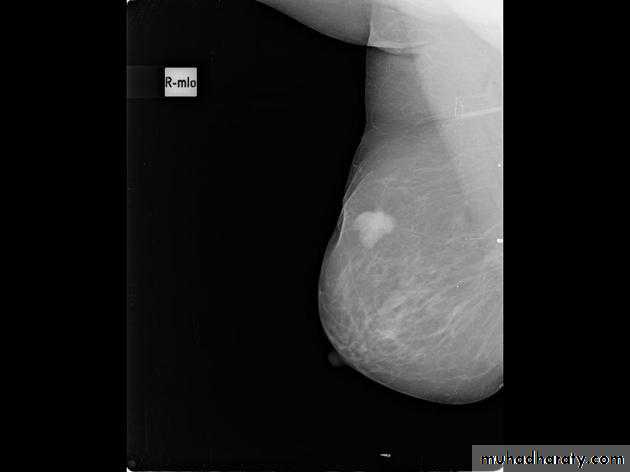

The mediolateral oblique (MLO) view is one of standard mammographic views. It is the most important projection as it allows to depict most breast tissue.

The craniocaudal view (CC view), is one of the two standard projections in a screening mammography. It must show the medial part as well the external lateral portion of the breast as much as possible.

Mammography

The sensitivity of mammography for the detection of ILC reportedly ranges between 55-80% 8. Because of the limitations of mammography in detecting ILC, other modalities, such as sonography and MR imaging, are being used in evaluating clinically suspicious findings and known cancers to assess the extent of disease. ILC are more commonly seen on the craniocaudal (CC), compared to the mediolateral oblique (MLO).